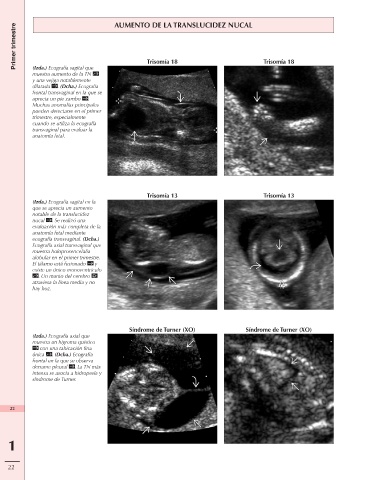

Primer trimestre AUMENTO DE LA TRANSLUCIDEZ NUCAL

(Izda.) Ecografía sagital que

muestra aumento de la TN Trisomía 18 Trisomía 18

y una vejiga notablemente

dilatada . (Dcha.) Ecografía

frontal transvaginal en la que se

aprecia un pie zambo .

Muchas anomalías principales

pueden detectarse en el primer

trimestre, especialmente

cuando se utiliza la ecografía

transvaginal para evaluar la

anatomía fetal.

Trisomía 13 Trisomía 13

(Izda.) Ecografía sagital en la

que se aprecia un aumento

notable de la translucidez

nucal . Se realizó una

evaluación más completa de la

anatomía fetal mediante

ecografía transvaginal. (Dcha.)

Ecografía axial transvaginal que

muestra holoprosencefalia

alobular en el primer trimestre.

El tálamo está fusionado y

existe un único monoventrículo

. Un manto del cerebro

atraviesa la línea media y no

hay hoz.

Síndrome de Turner (XO) Síndrome de Turner (XO)

(Izda.) Ecografía axial que

muestra un higroma quístico

con una tabicación fina

única . (Dcha.) Ecografía

frontal en la que se observa

derrame pleural . La TN más

intensa se asocia a hidropesía y

síndrome de Turner.